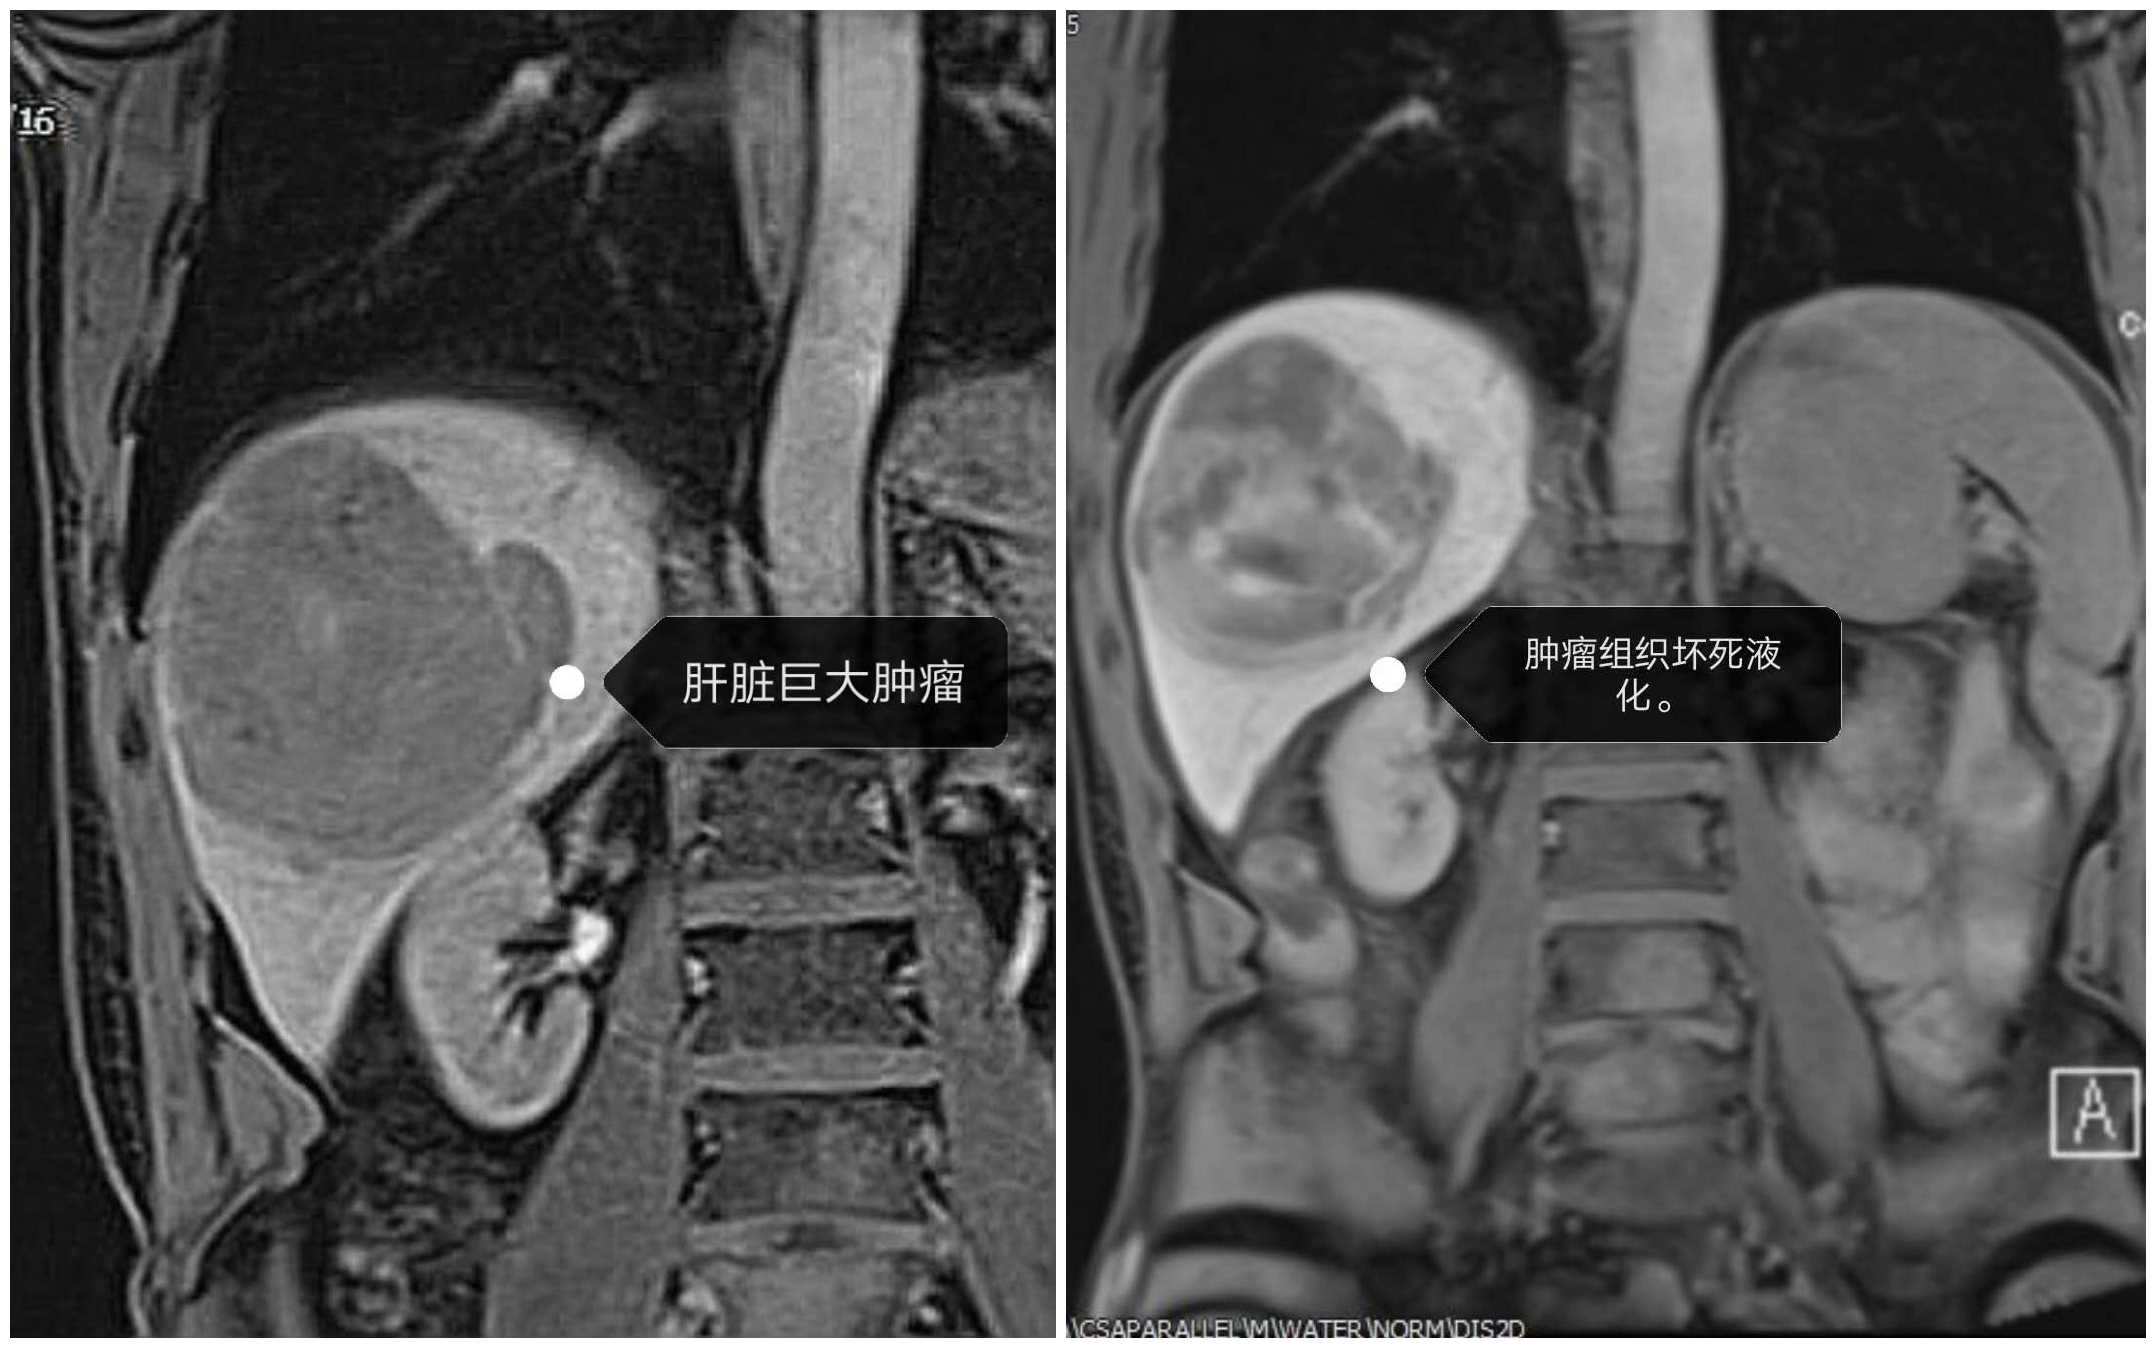

肝癌患者免疫治疗前后

近日,兰大二院肿瘤外科团队成功应用“免疫治疗”方案为罹患肛管肿瘤、巨大肝癌并多处转移的两位患者解除病痛。两位肿瘤患者因病情严重影响生活质量,甚至危及生命和精神健康,得知我院肿瘤外科陈昊教授团队治疗肿瘤疾病相关的信息后,慕名前来求医。陈昊教授在充分了解患者的病情及诉求后,为患者制定了完善的“免疫治疗”方案。经过治疗,效果显著,两位患者重获高质量的生活。“免疫治疗”的成功开展,标志着我院治疗肿瘤的理念进入崭新的领域。